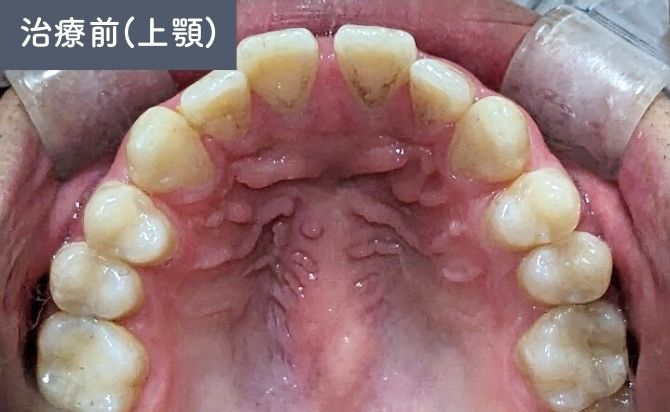

歯並びの変化(上)

治療終了時には、上顎前歯の歯間空隙が閉鎖され、前歯部の開咬も改善しました。上下前歯の前突感が軽減され、歯列弓も自然な形態に整っています。

前歯部の見た目が大きく改善しただけでなく、噛み合わせも安定し、機能面・審美面の両立が図られた症例となりました。